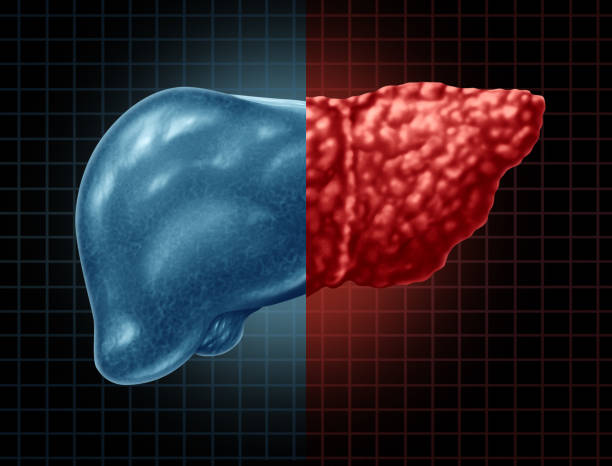

간경화 초기증상 10가지 총정리

간경화 초기증상은 증상이 나타나지 않거나, 미미한 증상만 나타나기 때문에, 무시하고 지나치기 쉬운 경우가 많습니다. 하지만, 이러한 초기 증상을 간과하면 질병이 진행되어 치료가 어려워질 수 있습니다. 따라서, 간경화 초기증상을 발견하면 적절한 검사와 치료를 받아 조기에 질병을 예방하고 치료할 수 있습니다. 따라서 이번 시간에는 간경화 초기증상에 대해 자세히 알아보도록 하겠습니다.